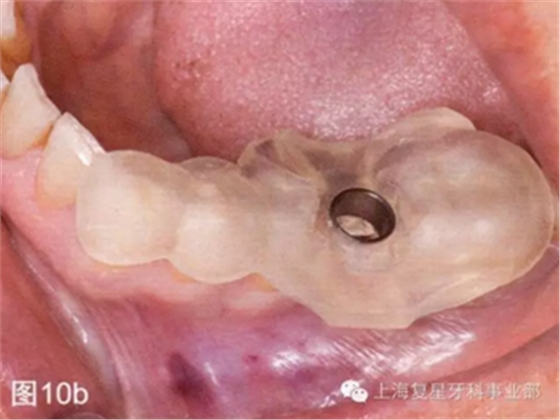

引導(dǎo)板一制作完成,就在模型上進(jìn)行試戴,檢查其有無不密合的地方以及在對(duì)引導(dǎo)板和BioHorizons引導(dǎo)手術(shù)工具包消毒之前有無手術(shù)進(jìn)入困難(圖10a)。

第二天患者就診進(jìn)行手術(shù)。用0.12%葡萄糖酸氯已定漱口水(Oralgene,Laboratorios Maver)含漱2分鐘后,進(jìn)行消毒和術(shù)區(qū)的準(zhǔn)備,在缺牙區(qū)(36#牙區(qū)域)的頰舌側(cè)和頂部進(jìn)行局部麻醉(2%鹽酸利多卡因和1:100000腎上腺素)。幾分鐘后,置入外科導(dǎo)板,在外科導(dǎo)板上的孔洞中置入中空的圓柱形金屬引導(dǎo)管,然后引導(dǎo)軟組織打孔器進(jìn)入,其轉(zhuǎn)速為1200rpm。然后去除引導(dǎo)板,用剝離子去除截面的軟組織,并浸泡在鹽溶液中(圖10b-d)。

圖10b:將外科導(dǎo)板放在手術(shù)部位